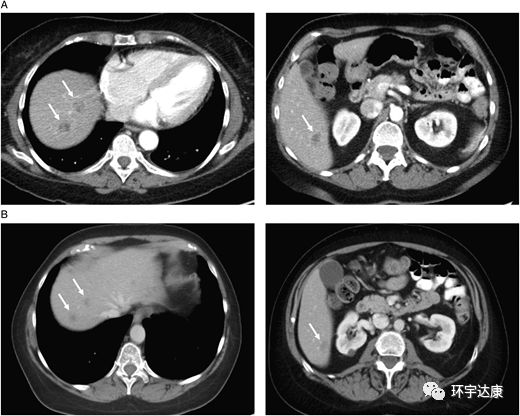

61岁的M女士被确诊为胰腺导管癌,胰腺体内有一个2.5cm的肿块,肝脏有1.2cm的转移病灶,基因检测发现NTRK1基因融合阳性,在接受拉罗替尼治疗后,胰腺和肝脏的病灶都明显缩小。

图1。

CT扫描:(A)治疗前(B)拉罗替尼治疗后